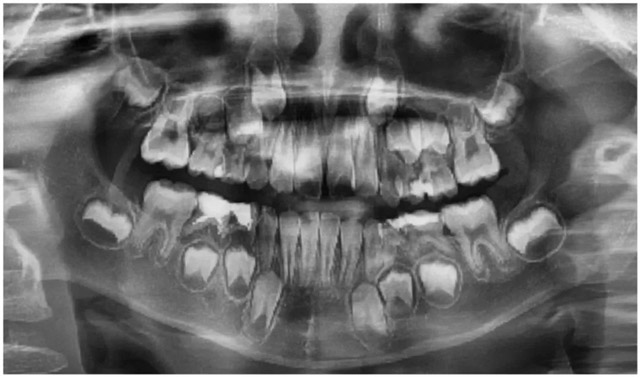

到院后,石佳桐医生为莉莉安排了全面检查,根据全景片、CBCT、口扫检查结果显示,莉莉存在牙弓狭窄、门牙唇倾、深覆盖等问题,这些问题已经影响到了她的正常咬合,需要进行早期矫正干预。

莉莉口腔全景片(替牙期,牙齿拥挤)